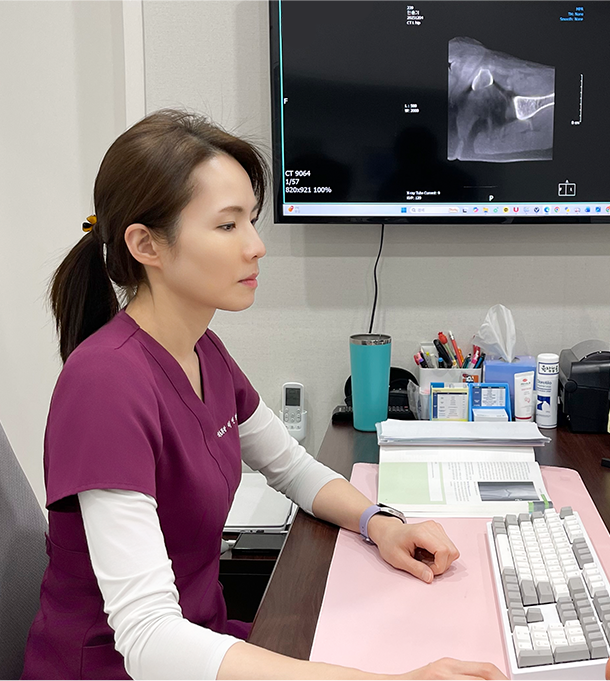

환자에게 꼭 필요한

진료만 제공합니다

초음파로 병변 확인

초음파로 병변 확인

정상 조직 손상 최소화

정상 조직 손상 최소화

방사선 노출 최소화

방사선 노출 최소화

미세 병변까지 정밀 확인

미세 병변까지 정밀 확인

3D 입체 영상 분석

3D 입체 영상 분석

빠르고 정확한 진단

빠르고 정확한 진단

실시간 영상 유도 시술

실시간 영상 유도 시술

신경·관절 위치 정밀 확인

신경·관절 위치 정밀 확인